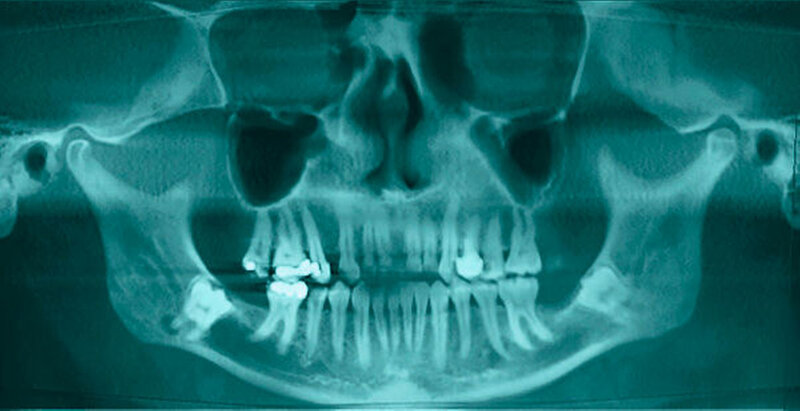

Eine 47-jährige Patientin wurde zur Entfernung der komplett retinierten Zähne 38 und 48 überwiesen. An der Wurzelspitze des Zahnes 48 fiel zusätzlich eine periradikuläre Transluzenz auf, die zur Indikationsstellung der Entfernung der Zähne führte (Abbildungen 1 und 2).

Aufgrund der engen Lagebeziehung der Weisheitszähne zum Nervus alveolaris der jeweiligen Seite wurde zur weiterführenden Diagnostik eine digitale Volumentomografie durchgeführt.

In der aus der digitalen Volumentomografie herausgerechneten Panoramaschichtaufnahme analogen Darstellung kann man schön die Alteration des Nervverlaufs in unmittelbarer Nachbarschaft zu den Weisheitszähnen erkennen. Der Nerv taucht von proximal kommend noch hinter dem Zahn liegend in die Tiefe, um dann auf Höhe der distalen Wurzel wieder in einem geraden Verlauf nach vorne weiter zu ziehen.

Eine Verletzung des Nervus alveolaris inferior bei Weisheitszahnentfernung findet sich überproportional häufig in Fällen, in denen auf der Panoramaschichtaufnahme Zeichen zu erkennen sind, wie eine Veränderung des Verlaufes des Nervus alveolaris inferior (Abbildungen 1 und 2), bei überlagerungsbedingter erhöhter Transluzenz im Bereich der Überprojektion von Wurzel und Nerv und bei Unterbrechung der kortikalen Begrenzung des Nervkanals [Blaeser et al., 2003]. Alle diese Kriterien lagen im vorliegenden Fall vor. In der weiterführenden digitalen Volumentomografie ist zu erkennen, wie der Nerv zwischen den Wurzeln liegend hindurchzieht.